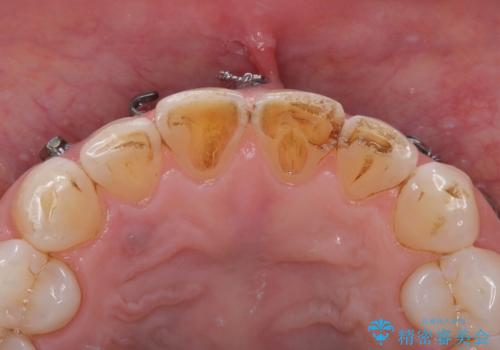

まず仮歯に置き換え、最終的な被せものの前に仮歯で形などを調整します。

その後精度の高いシリコーンによる型どりを行います。